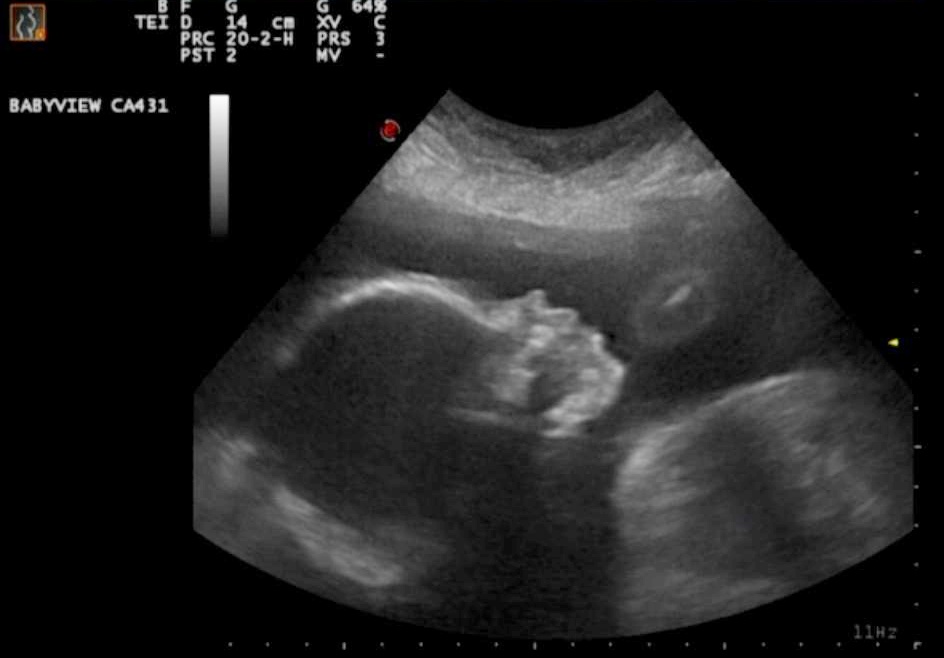

A ultrassonografia morfológica tem o intuito de avaliar a morfologia do bebê, ou seja, a sua forma como um todo. De maneira detalhada, todas as partes do bebê são avaliadas, incluindo as internas como órgãos e estruturas intracranianas. É importante ressaltar os dois períodos para a realização da ultrassonografia morfológica: um no primeiro e outro no segundo trimestre de gestação.